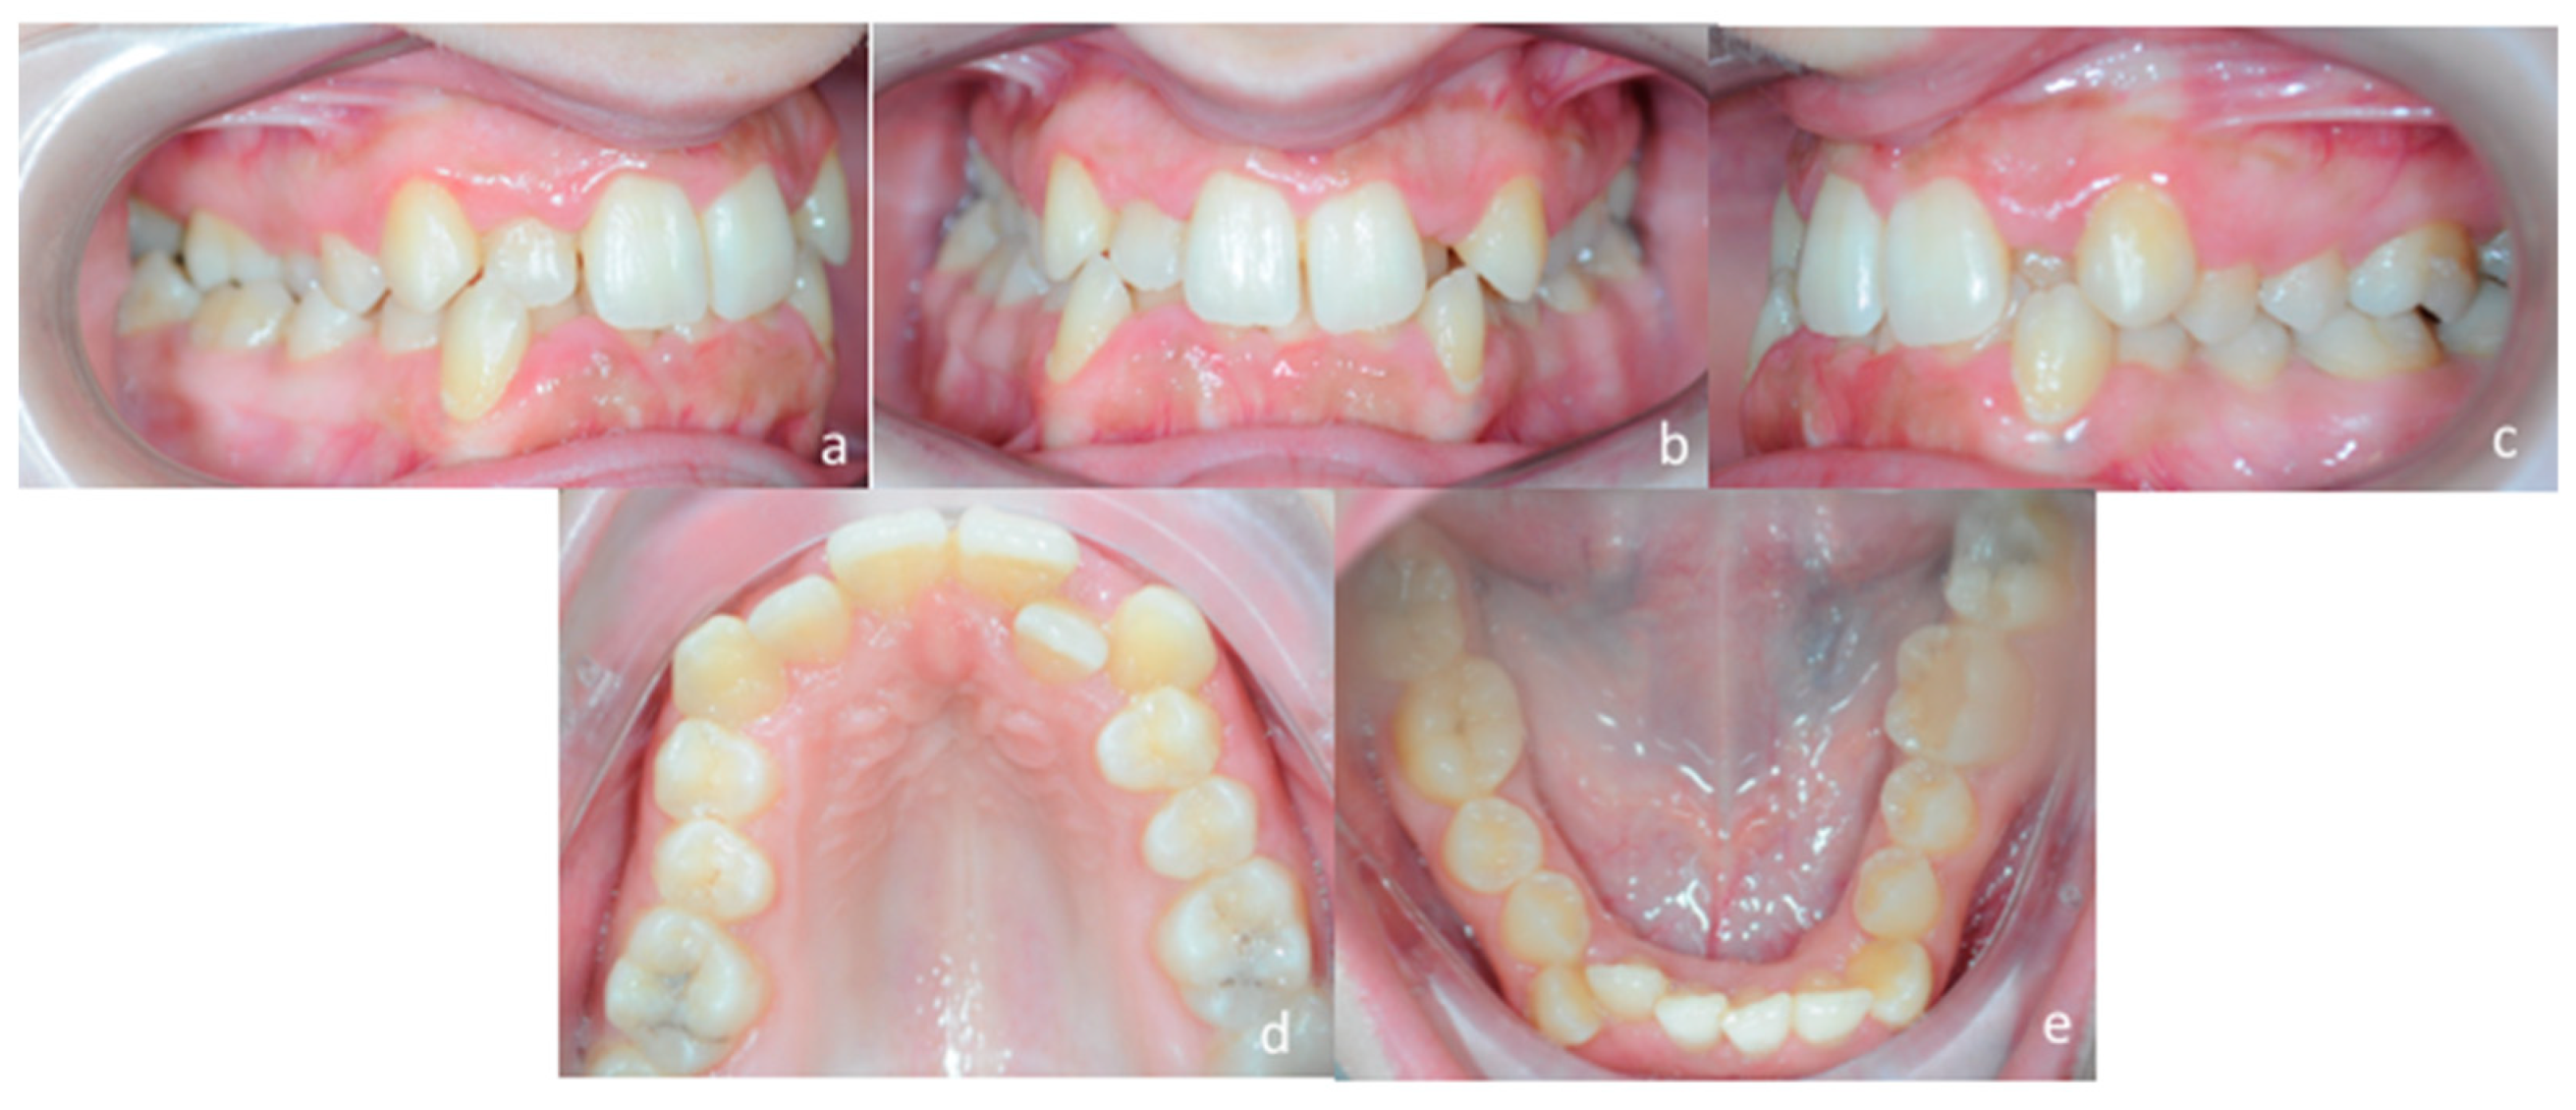

3.1. Diagnosis and Treatment Plan

3.2. Digital Workflow for Planning MSE Device